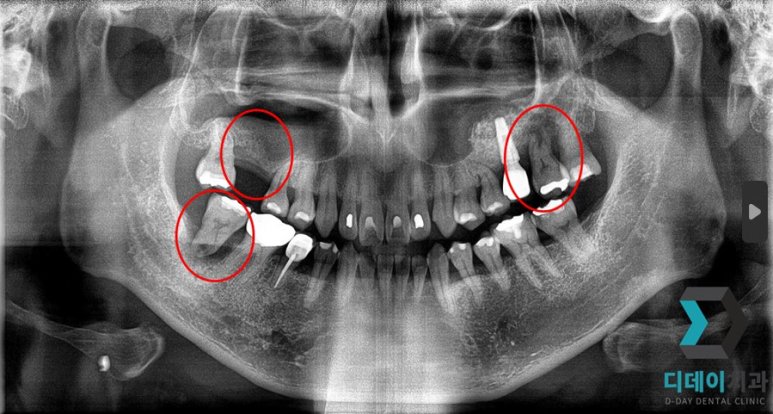

<전 2022-02-23>

<후 2022-10-14>